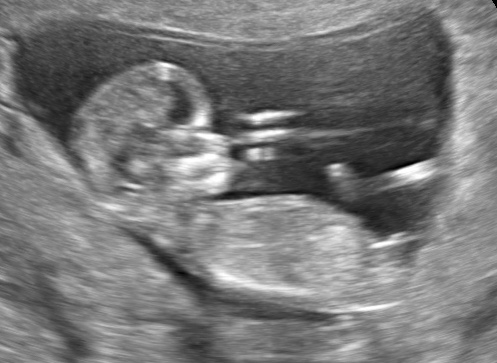

34 weken

Een echo na 34 weken.